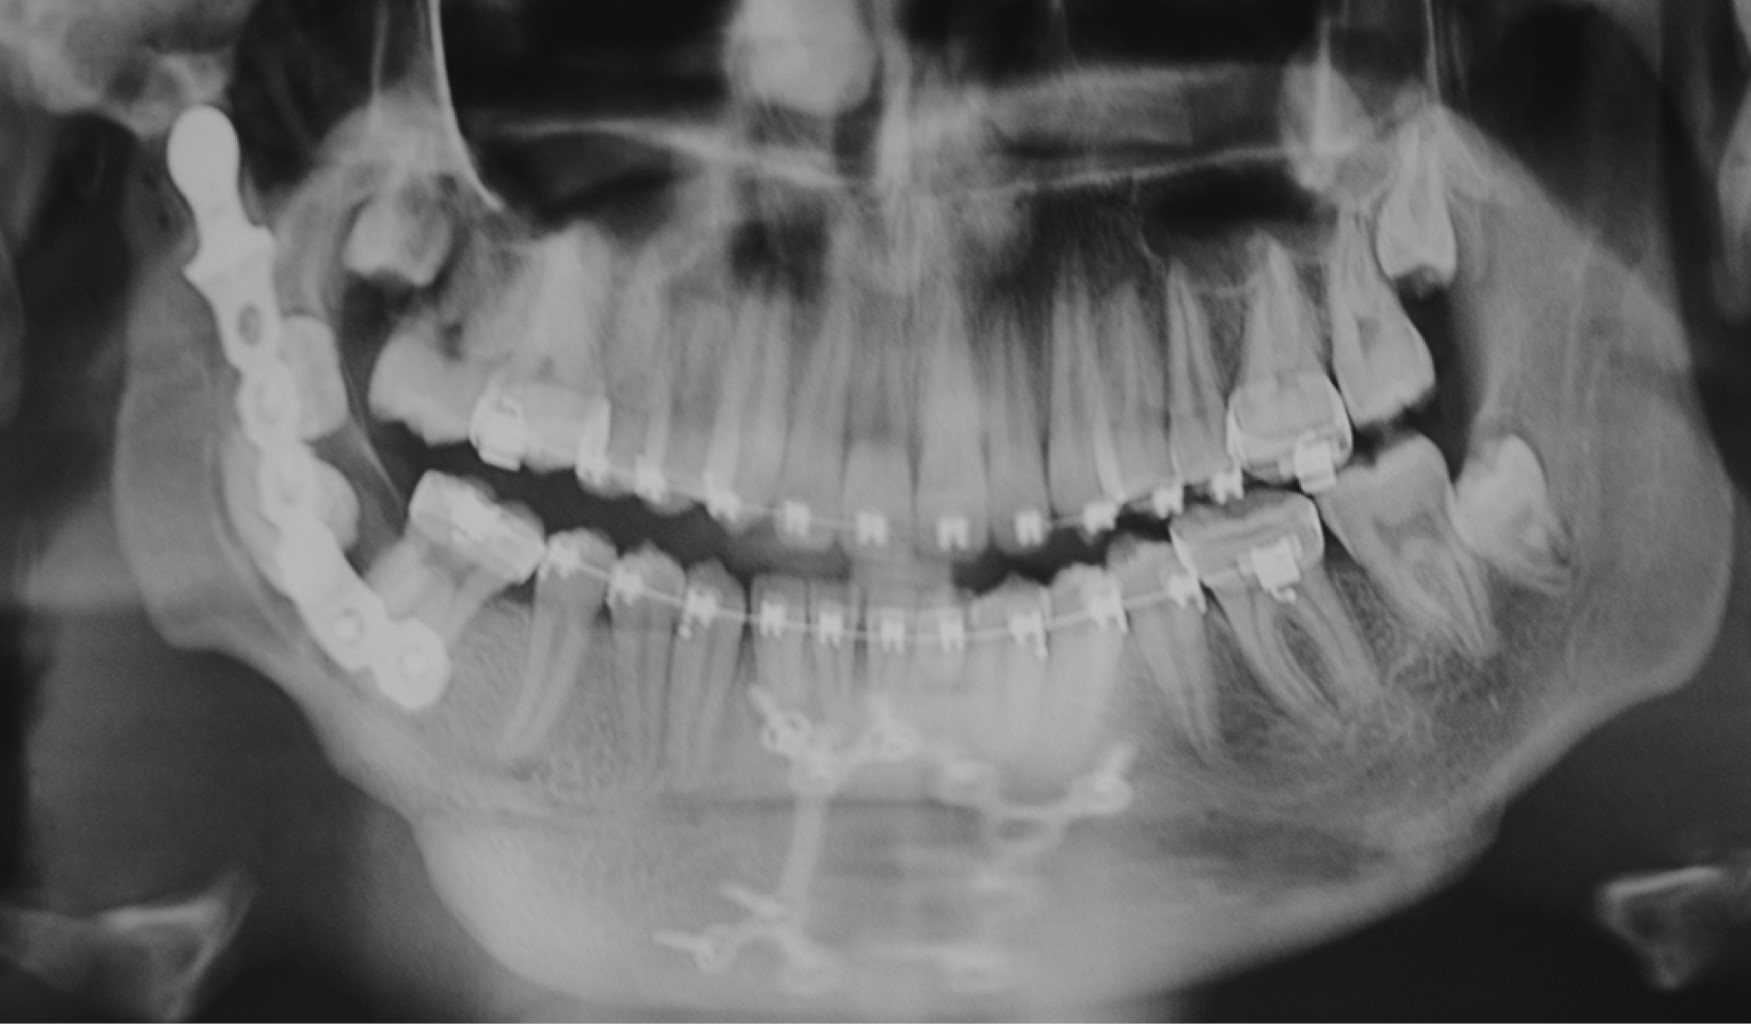

Se trata de paciente masculino de siete años de edad atendido en la Unidad Médica de Alta Especialidad (UMAE) No. 71 del Instituto Mexicano del Seguro Social, en la ciudad de Torreón, Coahuila, México. Acude por presentar imposibilidad de la apertura bucal desde la edad de cinco años, teniendo como único antecedente de importancia traumatismo facial al estar jugando y caer de su propia altura, evolucionando con progresiva limitación de apertura bucal hasta no poder abrirla en lo absoluto. A la exploración física, nula apertura bucal, aspecto facial con mínima alteración estética, micrognatia mandibular sin impacto estético importante (Figura 1). La radiografía inicial muestra anquilosis temporomandibular bilateral (Figura 2). Bajo anestesia general, intubación nasal con fibroscopio, se realiza liberación bilateral de anquilosis temporomandibular eliminando fragmentos óseos anquilosados y colocando prótesis metálicas de cavidad glenoidea de aleación cromo, cobalto, molibdeno (Figura 3), logrando adecuada apertura bucal sin complicaciones qué comentar (Figura 4). A la edad de 11 años se colocan prótesis metálicas de cóndilo de manera bilateral del mismo metal y mentoplastia de avance. Radiografía del paciente a la edad de 23 años (Figura 5).

A la edad de 25 años se realiza elevación de segmento anterior maxilar para corrección de exceso maxilar vertical sin complicaciones. Los abordajes quirúrgicos fueron preauricular bilateral, y submandibulares para la colocación de las prótesis, las cuales se fijan a hueso con tornillos de titanio, para la mentoplastia se utiliza abordaje en fondo de saco vestibular inferior. Para la elevación de la premaxila se utiliza abordaje en fondo de saco superior anterior. Apertura bucal y aspecto facial adecuados (Figura 6).

Figura 5